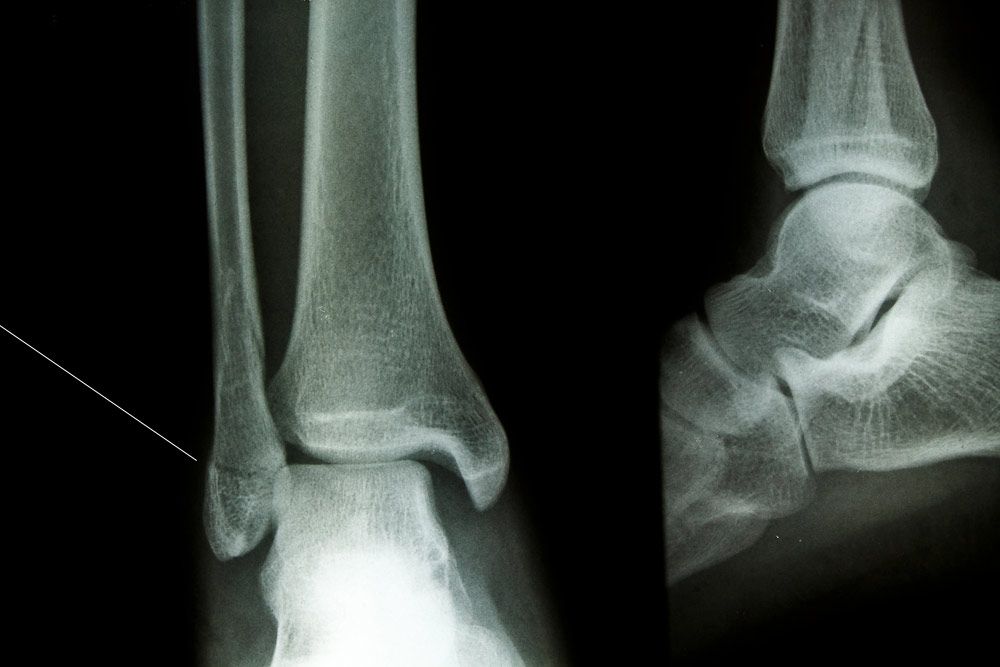

Before prescribing the appropriate treatment, our doctors will search for signs of a fracture using the latest technology and x-ray imaging to determine whether surgery is needed. As with any other procedure at Advanced Foot & Ankle Specialists, each fracture treatment plan is designed with the individual patient in mind. As such, every treatment will be different. Your options may include casting or surgery.

The ankles are among the most frequently fractured joints in the body. Ankle fractures range from minimal fractures to shattering of the tibia, fibula, or both bones. Many patients mistake ankle fractures for sprains, so it is important to see a doctor for an official diagnosis soon after the injury occurs. Common symptoms of an ankle fracture include: